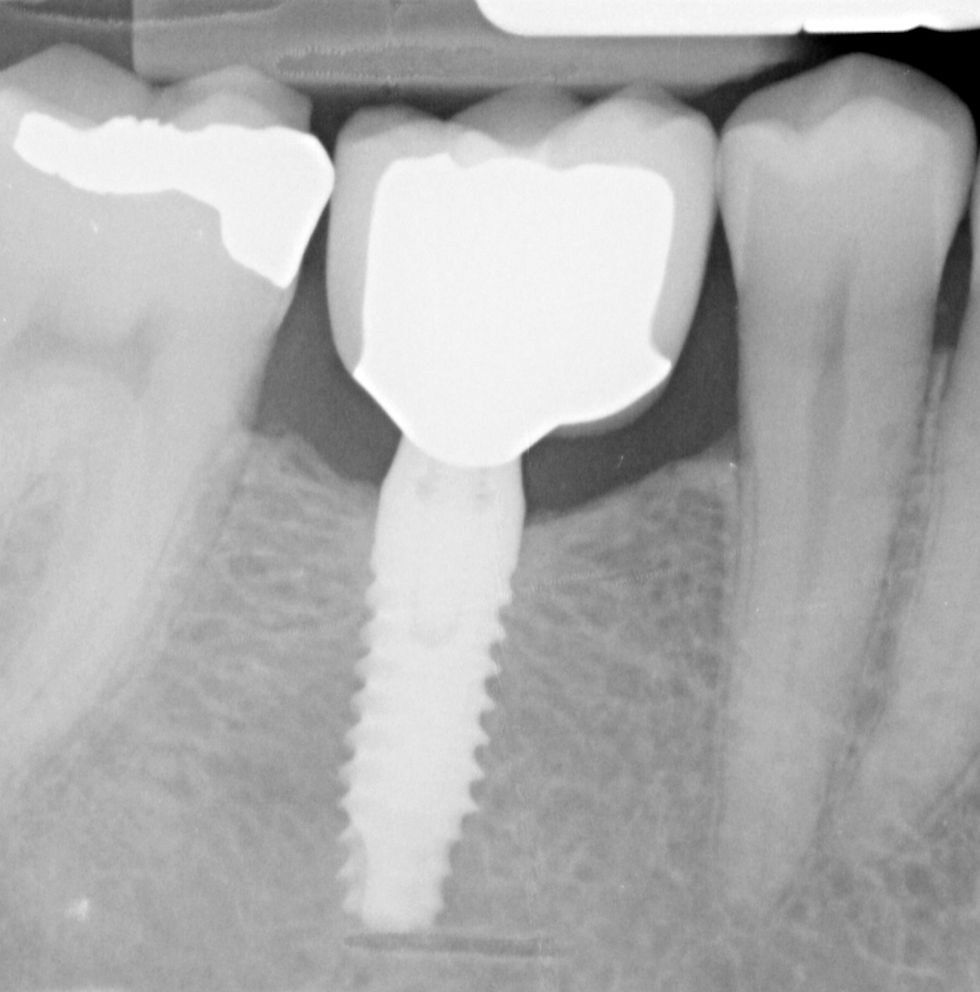

La morfologia convergente del collo Prama permette di recuperare la porzione di tessuto molle che con un impianto transmucoso tradizionale verrebbe occupata dal titanio del collo implantare. La convergenza di Prama fa sì che i volumi intorno alla porzione coronale dell’impianto vengano invece riempiti di coagulo e di importanti fattori di ricrescita, che si trasformano in tessuti molli spessi e funzionali.

L'ispessimento della gengiva che circonda il collo Prama rappresenta un beneficio indiscusso, soprattutto nei pazienti con biotipo più sottile, nei quali questo innovativo impianto apporta un ispessimento dei tessuti molli senza ricorrere a terapie rigenerative.

La stabilizzazione del connettivo, resa possibile dalla morfologia convergente e dalla microrigatura UTM, fa sì che tutto ciò che vi è al di sotto rimanga protetto e isolato da potenziali attacchi batterici, e che quindi l’osso si mantenga preservato in maniera efficace e a lungo, come ampiamente dimostrato dalla clinica.